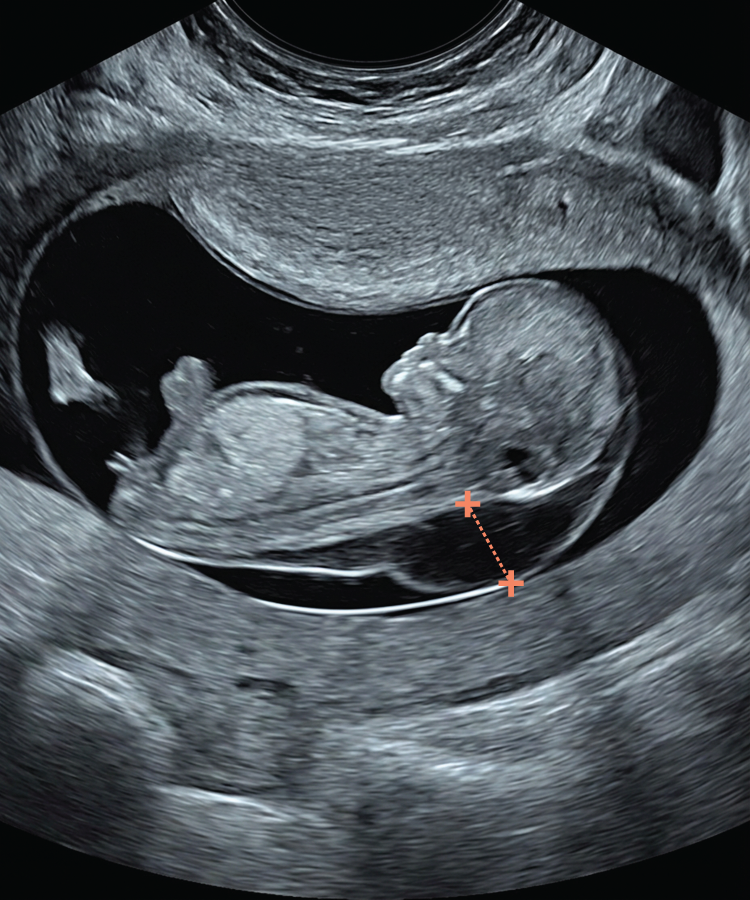

Midline Section: Full CRL view showing head and trunk in mid-sagittal section. The fetus may be face-up or back-up, as long as all mid-sagittal criteria are met.

Visualise: forehead and echogenic nasal tip, brainstem with typical “Z” shape, 4th ventricle and nuchal region

Skin line must be clearly seen, either separated from or merged with amnion. Spine must be straight.

Magnification: The fetal body should fill >60% of the screen.

Calliper Placement: Callipers should be placed on the inner borders of the nuchal translucency. Measurement must be perpendicular to the skin surface (crossbar orientation).